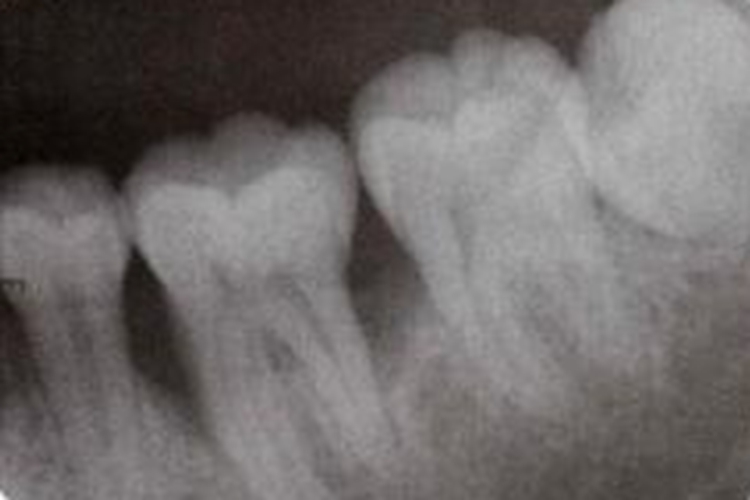

牙槽骨吸收常通过X线片观察,主要显示牙齿近远中的骨质情况。牙周炎的骨吸收最初表现为牙槽嵴顶的硬骨学板消失,或嵴顶模糊呈虫蚀状。嵴顶的少量吸收使前牙的牙槽间隔由尖变平或凹陷,在后牙则使嵴顶由宽平变凹陷,以后牙槽骨高度降低。牙槽嵴顶到釉牙骨质界的距离超过2mm,可视为牙槽骨吸收。